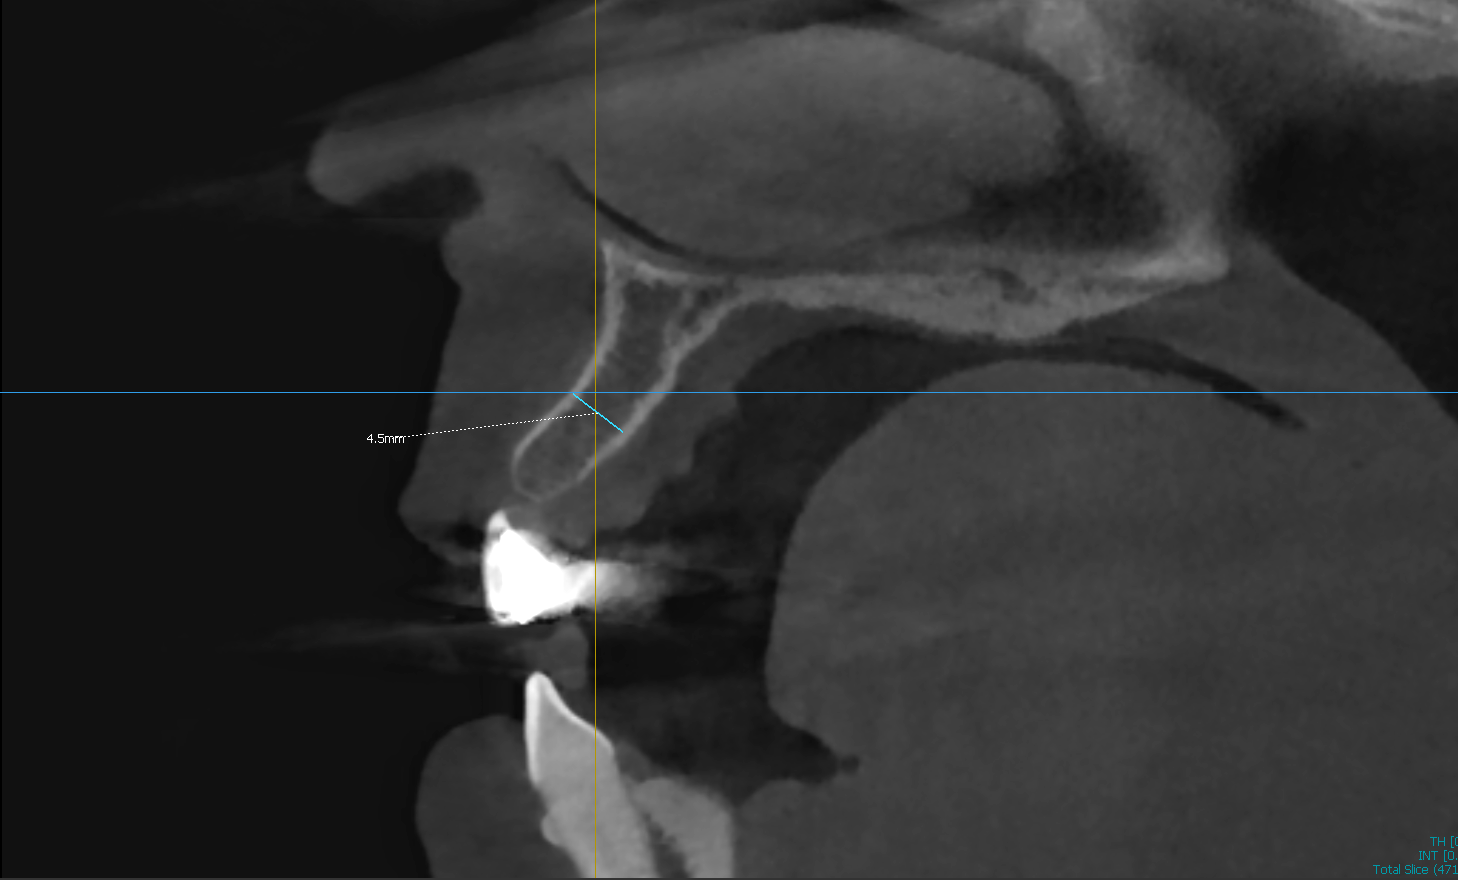

Challenge: Knife-edge ridge in the anterior maxilla presenting with only 4.5mm of width. Insufficient bone volume for implant placement without thread exposure.

Solution: Guided Bone Regeneration (GBR) utilizing particulate graft, resorbable membrane, and fixation tacks to horizontally widen the ridge.

Outcome: Ridge width increased to 8.4mm. Site successfully prepared for ideal, prosthetically-driven implant placement.